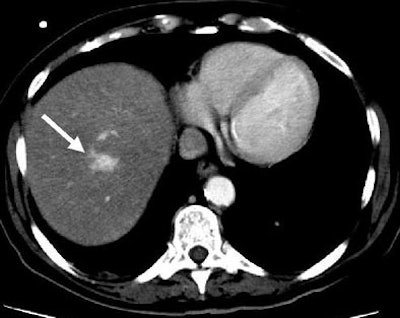

| Another patient with fever after prolonged neutropenia. Above, arterial-phase CT shows a type 2b lesion (arrow). Below, portal-venous phase fails to show a lesion. |

![]() |